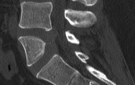

Im Zentrum für Orthopädie und Unfallchirurgie wird das gesamte Spektrum der Verletzungen und Erkrankungen des Bewegungsapparates von Kindern und Jugendlichen behandelt. Regelmäßig findet unsere kinderorthopädische Ambulanz statt. Die Behandlung oder operative Therapie ist in die jeweiligen spezialisierten Fachbereiche eingegliedert.